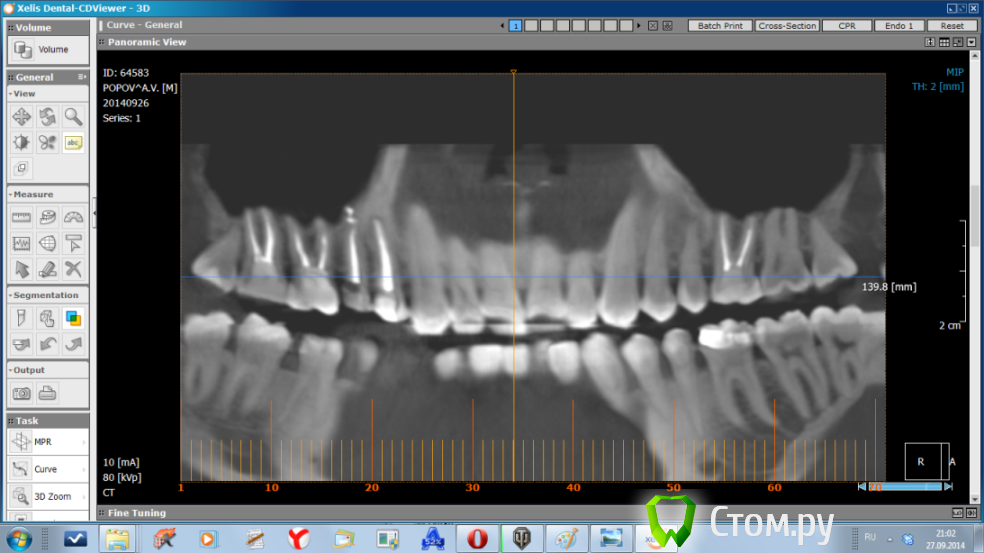

WHEELSS Опубликовано 30 сентября, 2014 Поделиться Опубликовано 30 сентября, 2014 (изменено) Здравствуйте, посмотрите пожауйста снимки сделанные из КТ. Интересует зуб верхняя правая пятерка (с одним корнем). Как запломбирован канал? Нет ли кисты?Зуб болит каждый день, уже на протяжении двух месяцев. Изменено 30 сентября, 2014 пользователем WHEELSS Ссылка на комментарий

dr-krasnov Опубликовано 30 сентября, 2014 Поделиться Опубликовано 30 сентября, 2014 Зуб запломбирован с выведением пломбировочного материала за пределы апикального отверстия, один из фрагментов находится, судя по всему, в толще слизистой оболочки верхнечелюстного синуса, что вызывает воспаление и может объяснить ваши симптомы. 1 1 Ссылка на комментарий

SDC Опубликовано 1 октября, 2014 Поделиться Опубликовано 1 октября, 2014 (изменено) Дайте, пожалуйста, срезы КТ в трансверсальной (горизонтальной) проекции. А еще лучше - выложите zip-папку Data (c .dcm файлами) на облако и дайте ссылку на скачивание.Скачал, открыл. Вижу одну единственную маленькую причину, которая сначала привела к остаточному пульпиту, а сейчас к хр. периодонтиту. (если, конечно, мы рассматриваем 15 зуб, как единственный причинный) Это доп.канал, расположенный палатинально. очень часто анатомия верхний 5-х зубов именно такова: один магистральный канал, который в апикальной части расходится на 2, "ласточкин хвост". Срез в апикальной части корня, где контурируется 2 слившихся корня, намекает на подобную анатомию.Это предположение получит подтверждение при:1. Наличии чувствительности на холодное и/или горячее в первые дни после эндолечения 15 зуба. (из анамнеза)2. Положительной динамике после повторной обработки канала.3. При визуализации бокового (палатинального) ответвления магистрального канала в микроскоп. http://s017.radikal.ru/i432/1410/b0/89dec2d707be.jpghttp://s019.radikal.ru/i624/1410/12/8beb2b221607.jpghttp://s009.radikal.ru/i308/1410/a2/22f792e49f66.jpg Изменено 1 октября, 2014 пользователем SDC 1 1 Ссылка на комментарий